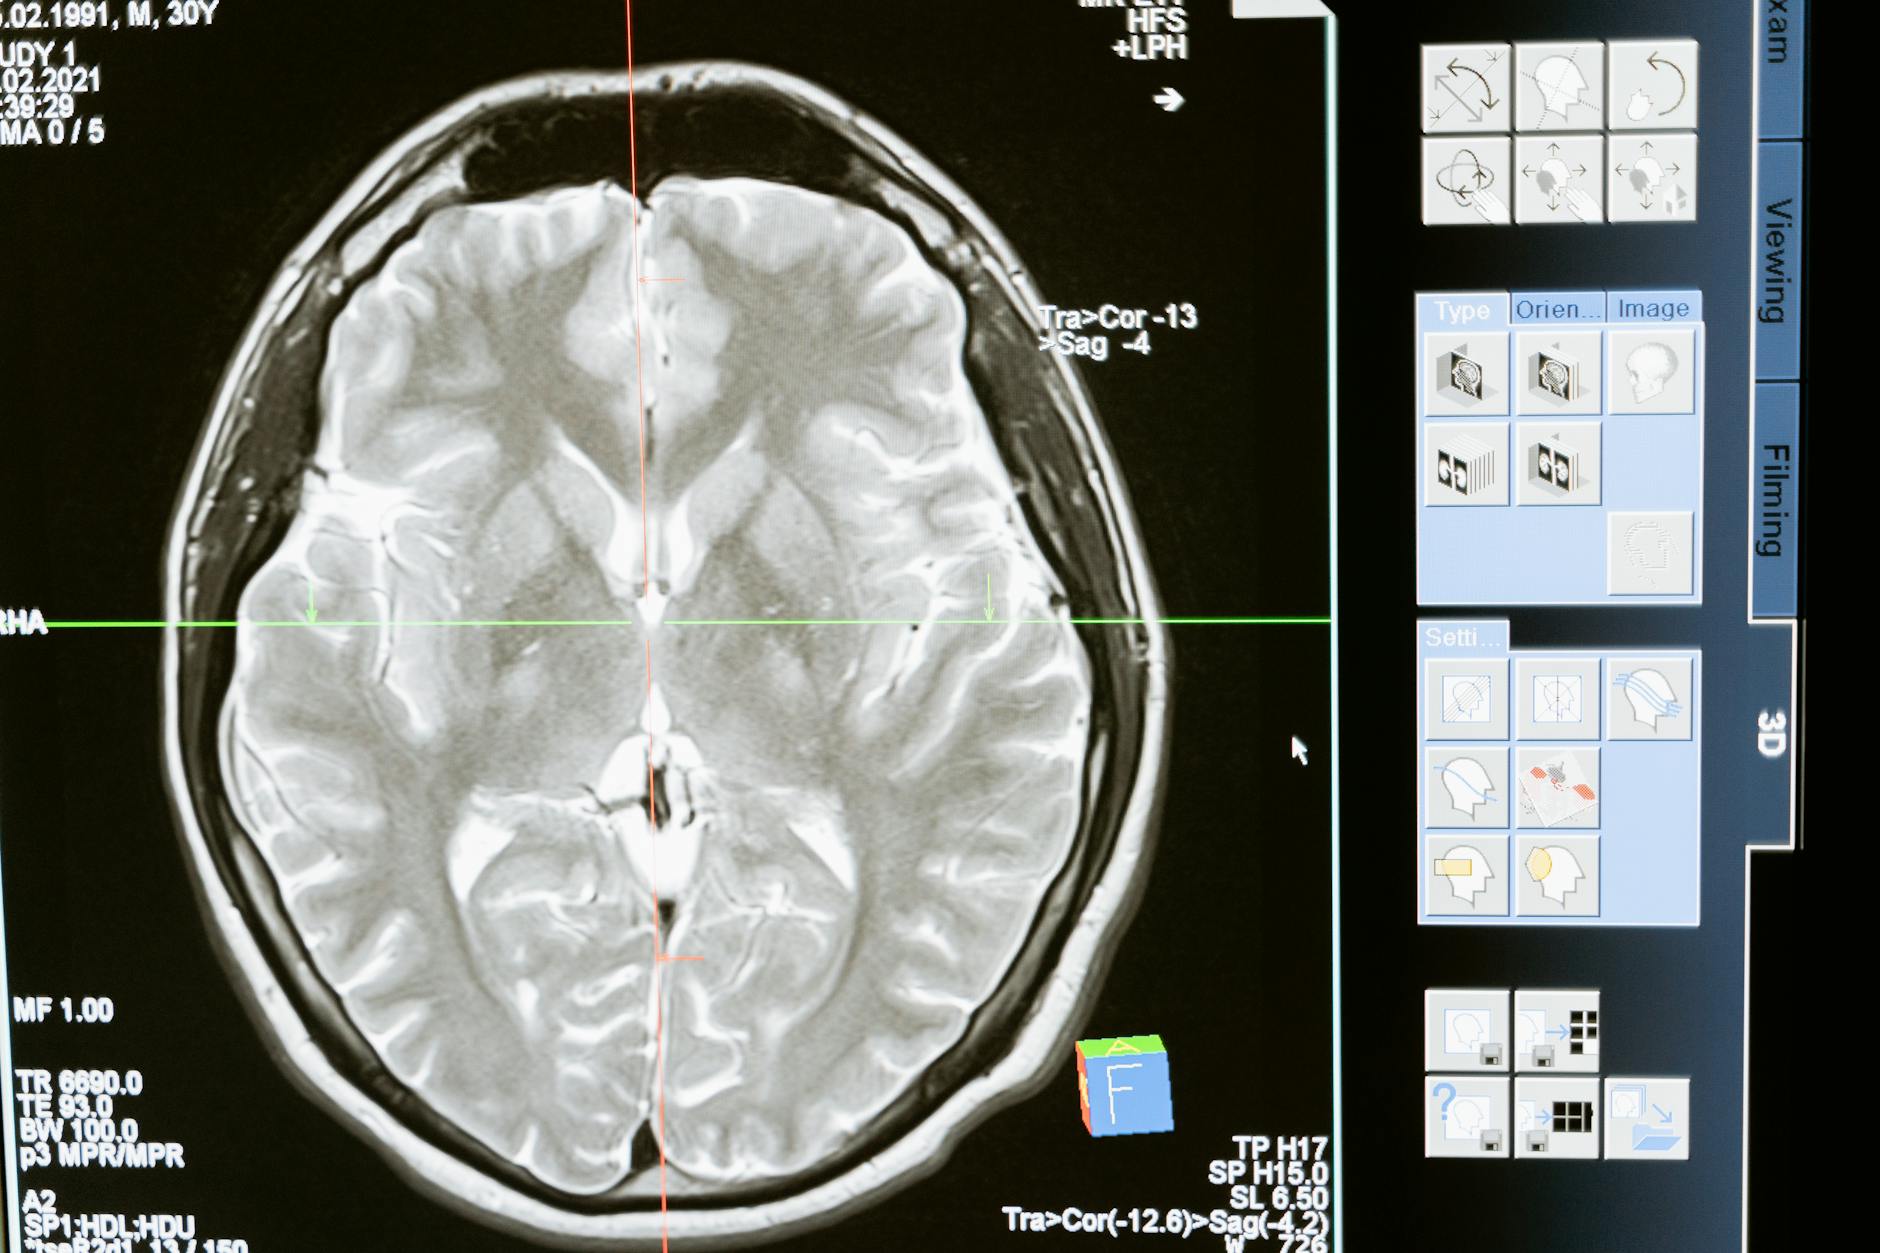

technology computer head health

Molecular Hydrogen: A Promising Therapy for Neurological and Neurodegenerative Conditions

Neurological disorders and neurodegenerative diseases represent some of the most challenging conditions in modern medicine, with limited treatment options and often progressive deterioration. Recent research has highlighted molecular hydrogen (H₂) as a promising therapeutic agent for these conditions, offering neuroprotective benefits through multiple mechanisms. This article explores the current evidence supporting hydrogen’s application in neurological health and its potential to transform treatment approaches.